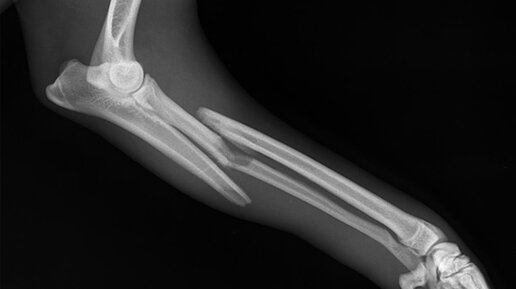

Перелом! Первая помощь.

Основные виды переломов Вид перелома зависит от характера травмы, направление вектора силы действующей на скелет пострадавшего, и его положение в момент травмы закономерно указывает на характер перелома. Так при падении на вытянутую руку происходит перелом лучевой кости в типичном месте, при ударе бампером легковой машины, развивается характерный "бамперный перелом" и т.п. ПЕРЕЛОМЫ ЧЕЛЮСТИ Если пострадавший в сознании, посадить, наклонить немного вперед, приложить подушечку или сложенную в несколько слоев ткань, чтобы прижать челюсть (лучше, если это сделает сам пострадавший)...

У него там не ЗАКРЫТЫЙ, а ОТКРЫТЫЙ перелом.